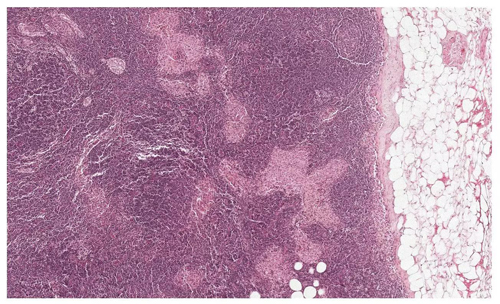

▲你能從這張切片中,找到哪些是腫瘤,哪些是正常組織,哪些是看起來很像腫瘤的正常組織嗎?(圖片來源:谷歌)

許多疾病的診斷依賴于病理學(xué)家對(duì)于組織切片的分析,這也成為了疾病診斷的黃金標(biāo)準(zhǔn)。對(duì)乳腺癌患者來說,病理學(xué)家將用顯微鏡鏡檢的方法,仔細(xì)觀看乳腺旁的淋巴結(jié),尋找腫瘤的痕跡。根據(jù)鏡檢的結(jié)果,病理學(xué)家將告訴患者乳腺癌所處的階段,以及腫瘤是否發(fā)生轉(zhuǎn)移。這些分析直接決定了患者要采取的治療手段與疾病管理方法。據(jù)估計(jì),全美每年有23萬乳腺癌患者需要接受這樣的診斷,聆聽醫(yī)生對(duì)她們命運(yùn)的宣判。